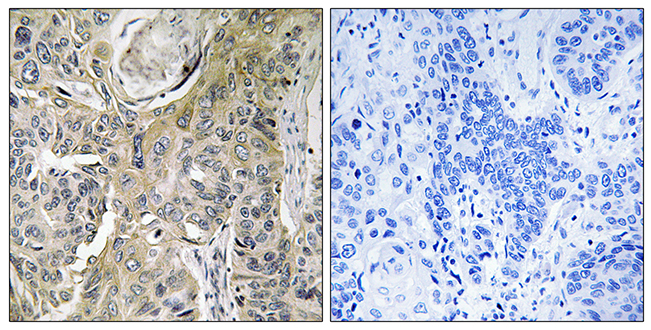

ApplicationsImmunoHistoChemistry

ReactivityHuman

- SizePrice